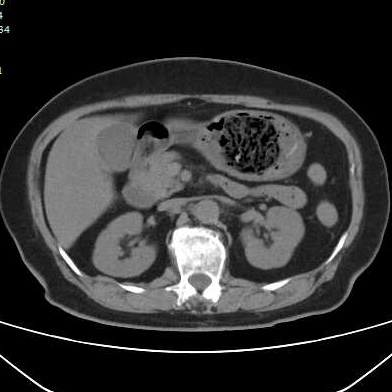

最近有几个吃山楂后形成胃结石的病历,第一个,老年女性,突发腹痛2天,持续性钝痛,阵发性加重,伴恶心,呕吐胃内容物,性状无异常,呕吐后无缓解,入院后抑酸治疗效果不理想,CT如下图。

考虑胃内结石,予以碳酸氢钠和可乐口服,第二天症状缓解,因为有别的问题,没有胃镜证实。

因为非影像专业,自己总结肠道植物性结石的特点,混杂密度,多数边缘规则,与正常胃、肠壁结构分界清晰,临床考虑多数急性起病,关键是要问近期是否有大量食用柿子、山楂、黑枣等富含鞣酸食物。